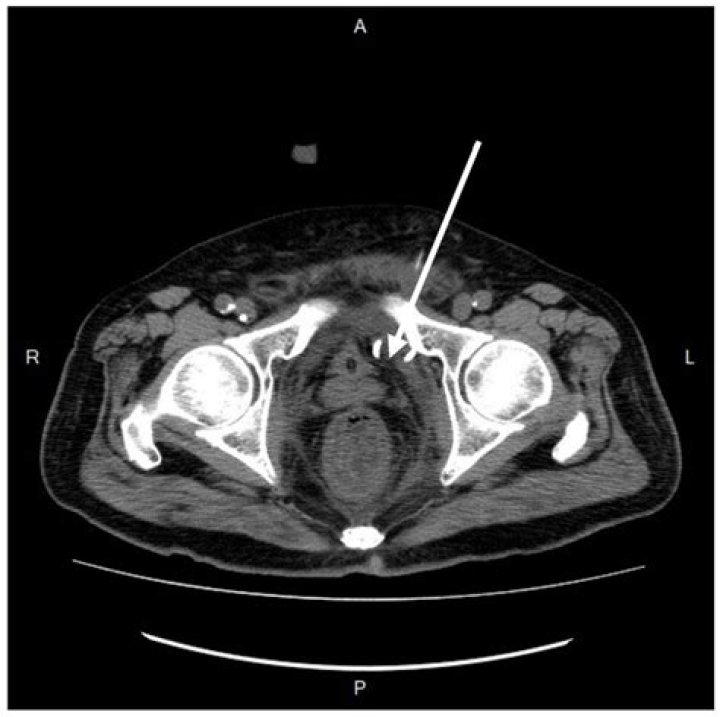

Ischiorectal abscesses are the next most common type. These abscesses form when suppuration transverses the external anal sphincter into the ischiorectal space. An ischiorectal abscess may traverse the deep postanal space into the contralateral side, forming a so-called horseshoe abscess.

A horseshoe abscess is a particularly aggressive type of perianal disease in which there is an erratic pattern of spread in a ring-like fashion to the deep postanal or even preanal space and then to the bilateral ischiorectal fossae by way of Colles fascia.